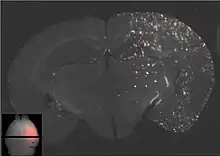

Les ultrasons peuvent être focalisés sur n'importe quel domaine du cerveau. C'est ainsi que l'on peut ouvrir la barrière hémato-encéphalique sélectivement sur des régions délimitées du cerveau. Les médicaments administrés pénétreront alors sur la zone ainsi ciblée[138]. On peut suivre le ciblage des zones par une IRM simultanée : il suffit d'administrer un produit de contraste IRM, comme du gadolinium convenablement chélaté, qui pénètre dans le cerveau à travers les parties de la barrière hémato-encéphalique ouvertes. Ces parties deviennent alors visibles en IRM. Les produits de contraste ne sont pas en mesure de franchir la barrière aux endroits où elle n'est pas ouverte.

Sur le modèle animal de la souris, on a utilisé des ultrasons focalisés dans le domaine de 0,5 à 2 MHz[139], avec de brèves impulsions de l'ordre de la milliseconde, répétées à intervalles de 1 s, pour une durée totale inférieure à une minute[140]. La fréquence optimale se situe au-dessous de 1 MHz[141]. La puissance acoustique instantanée est inférieure au watt, et donc la puissance moyenne de l'ordre du mW. Les microbulles utilisées sont en général des microbulles autorisées pour l'échocardiographie de contraste. Elles ont typiquement un diamètre de 3 à 5,5 μm, et sont composées typiquement d'albumine humaine, remplie d'octafluoropropane ou de gaz lourd semblable[142].

Le mécanisme de l'ouverture de la barrière hémato-encéphalique par utilisation d'ultrasons focalisés et de microbulles n'est pas encore complètement élucidé. L'interaction entre les ultrasons et les microbulles y joue un grand rôle, et conduit in vivo à toute une série d'effets biologiques[143]. Il semble qu'un grand rôle est joué par les forces de cisaillement créées par les microcourants. Ces microcourants eux-mêmes proviennent des oscillations des microbulles dans le champ d'ultrasons[143]. On sait déjà que les endothéliums peuvent réagir dynamiquement aux forces de cisaillement, et que ces forces de cisaillement sont une grandeur critique pour l'homéostasie[144]. Les vues en microscopie électronique des capillaires d'animaux ainsi traités présentent des signes aussi bien de transport transcellulaire que paracellulaire de molécules marqueurs (péroxydase du raifort). Le transport transcellulaire est la transcytose, tandis que le transport paracellulaire est initié par un processus complexe de désintégration, qui fait perdre leur fonction aux jonctions serrées[145].

La barrière hémato-encéphalique ainsi ouverte est perméable pour les médicaments de chimiothérapie de faible masse moléculaire, comme la doxorubicine[146], et des anticorps come le Trastuzumab[147],[148],[149]. La faisabilité de principe du transport dans le cerveau a été démontrée avec cette méthode même pour des gènes sur des modèles animaux[150],[142]. Le procédé d'ouverture de la barrière hémato-encéphalique par ultrasons et injection simultanée de microbulles en est encore à ses débuts. Jusqu'à présent, il n'a été testé que sur des animaux. L'expérience conduit à penser qu'il se passera encore de nombreuses années jusqu’à ce qu'il soit autorisé sur l’homme.